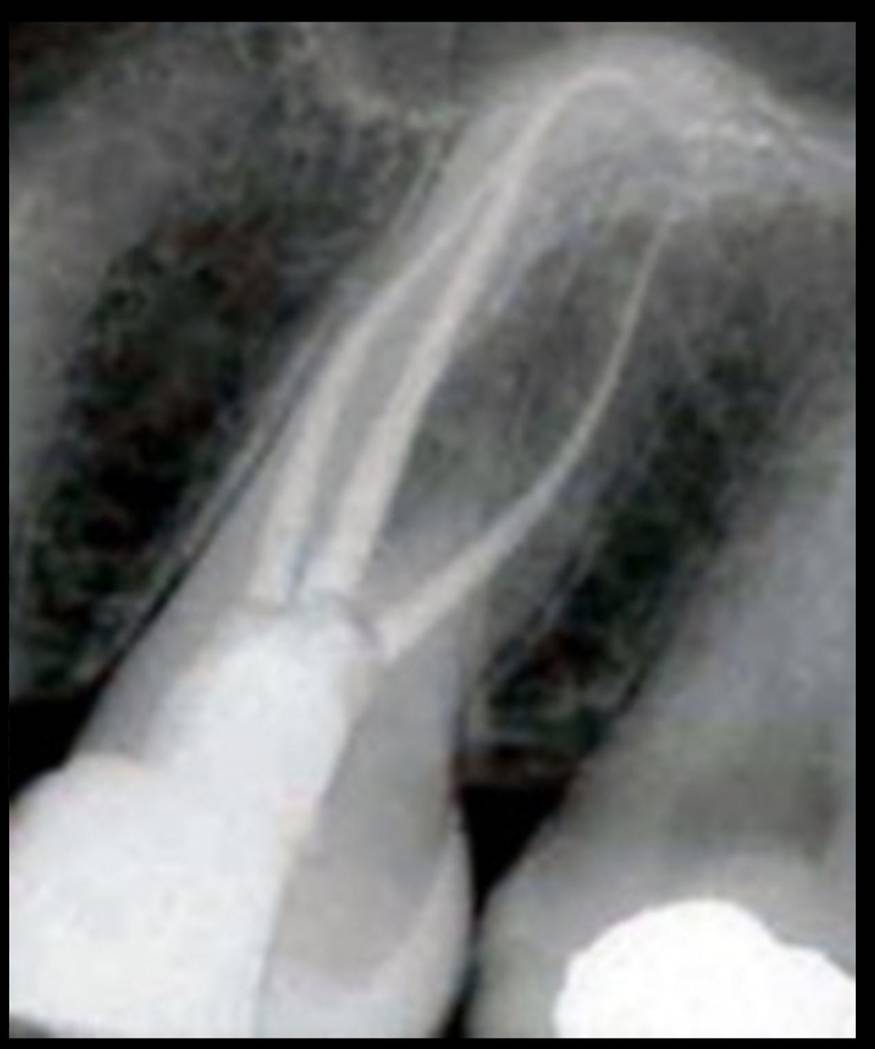

Apertura della corona fino ad arrivare alla camera pulpare (tale trattamento viene eseguito tramite anestesia locale). Si rimuove la polpa e si cercano i canali radicolari del dente, una volta trovati si estirpano i nervi. Si allargano e si puliscono i canali del dente, (tramite strumenti al Nichel titanio o strumenti manuali) prendendo anticipatamente le misure dei canali (per non uscire oltre apice). Si disinfettano i canali e si eseguono vari lavaggi tra un passaggio e un altro per elimininare il fango dentinale. Il medico a questo punto verifica la possibilità di chiudere definivamente i canali o lasciare il dente in prova, inserirendo nei canali un disinfettante e eseguendo una chiusura provvisoria. Al momento di chiudere il dente definivamente, questo viene preparato rieseguendo le misure dei canali da chiudere ed usando per la stessa lunghezza del canale, un cono di guttaperga del diametro necessario. Si scalda il cono in guttaperga e si inserisce nel canale. Durante il trattamento endodondico vengono effettuati una serie di esami radiografici per verificare i risultati, le lunghezze, la forma dei canali.

L'esame radiografico, fondamentale per porre diagnosi in odontoiatria, in endodonzia è irrinunciabile perché è l'unico strumento che ci permette di "vedere" all'interno della radice del dente, è quindi molto importante la possibilità di effettuare lastre con apparecchiature digitali che emettono un quarto della dose di raggi emessa da un radiografico tradizionale e che permettono di conservare la radiografia endorale in una cartella informatica del paziente senza possibili alterazioni nel tempo.